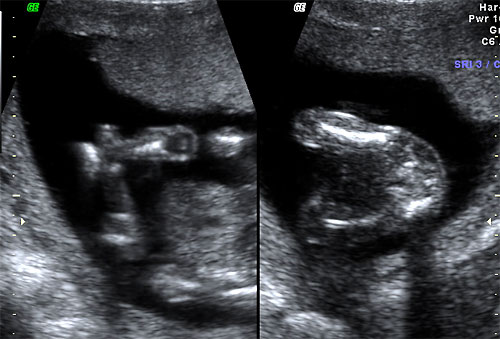

Normal 16 week abdominal anatomy |

Normal 16 week stomach |

Normal 16 week fetal cord insertion site |